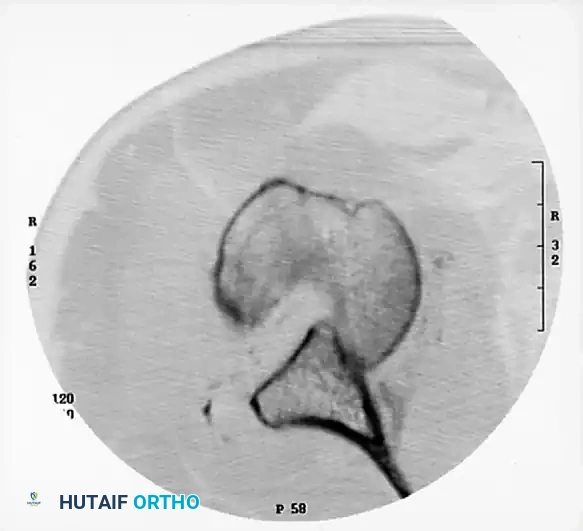

Standard Radiography

Initial evaluation must include a true anteroposterior (Grashey) view and an axillary view of the shoulder. The axillary view is non-negotiable, as it definitively confirms the direction of the dislocation and provides an initial assessment of the articular defects. If pain precludes a standard axillary view, a Velpeau axillary view should be obtained.

Advanced Cross-Sectional Imaging

Computed Tomography (CT), particularly with three-dimensional (3D) reconstruction techniques, is mandatory. CT is highly helpful in evaluating the complex bony injuries, quantifying glenoid bone loss, and precisely measuring the extent of damage to the articular surface of the humeral head.

Surgical Pearl: The degree of damage to the articular surface, as quantified on the preoperative CT scan, is the major determining factor in the surgical procedure selected. Defects involving less than 20-25% of the articular surface may be amenable to joint-preserving procedures (e.g., allograft reconstruction, transfer of the lesser tuberosity). Defects exceeding 40-50% typically necessitate prosthetic arthroplasty.